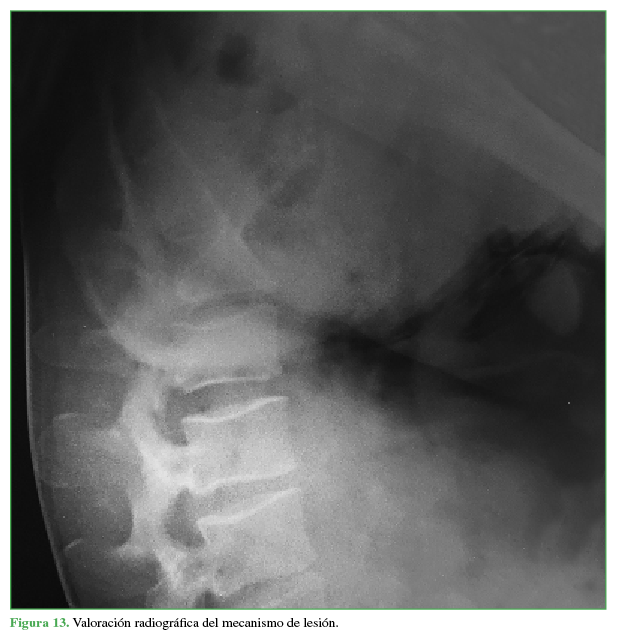

Mecanismo de lesión: “impactor sacropelviano”

En ambos casos presentados, los pacientes sufren el trauma secundario a la caída hacia atrás del binomio caballo-jinete, durante el “voleo” del animal, el caballo cae sobre su dorso aprisionando al jinete contra el suelo. El jinete queda atascado entre la cabalgadura y el suelo con la región lumbopelviana en máxima flexión hacia el zenit; de esta forma, recibe el peso del animal sobre los isquiones y el sacro (Tabla). El paciente en posición de hiperflexión permanece fijo con el platillo vertebral superior de S1 paralelo al suelo (Figuras 13 y 14), la pelvis y el sacro actúan como un verdadero “impactor” que resume las fuerzas del peso del caballo y su caída en la columna lumbar baja con la consiguiente fractura de tipo estallido de la cuarta vértebra lumbar.